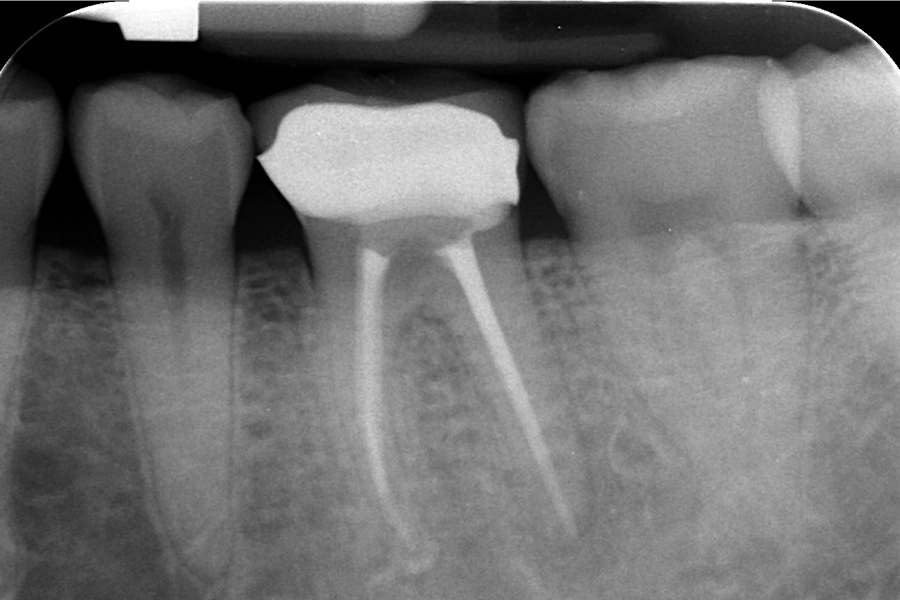

治療後